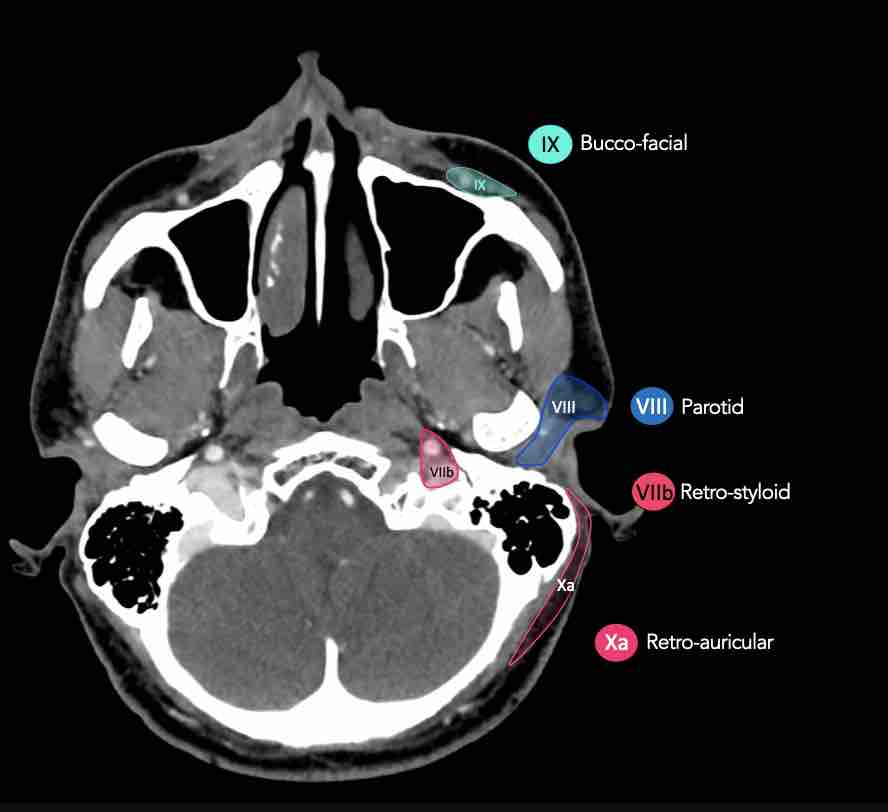

CT Scan Mặt Cắt Ngang (Axial CT)

Các lát cắt CT mặt phẳng ngang tương ứng với hình minh họa tổng quan.

Các lát cắt CT mặt phẳng ngang với hình ảnh chi tiết hơn.